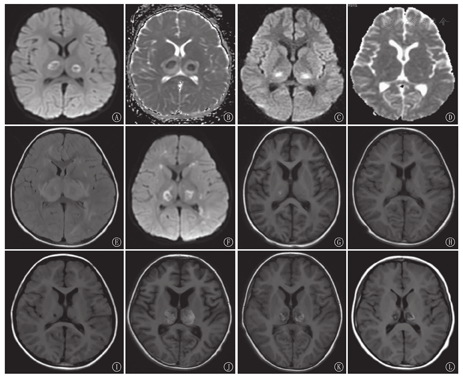

41例首次入院头颅MRI显示,病灶多呈对称分布,病灶累及部位:丘脑41例(100.0%)、侧脑室周围白质34例(82.9%)、脑干31例(75.6%)、基底核26例(63.4%)、大脑皮质及皮质下20例(48.8%)、小脑18例(43.9%)。累积部位数为(4.10±1.56)个。32例(78.0%)DWI示双侧丘脑中央低信号区周围环形高信号,最外层丘脑周围可见低信号区,ADC与之相反,呈"三色模式"(图1A,图1B);9例(22.0%)DWI表现为丘脑中央高信号及边缘低信号,ADC与之相反,呈"双色模式"(图1C,图1D)。34例幸存病例均在病程第2周、第1个月、第3个月、第6个月行头MRI随访(图2),24例MRI随访>1年。病程中28/34例(82.4%)头颅MRI显示出血,多发生在丘脑,病程2周内出现,后逐渐消失,6个月后大部分病例出血消失(图1E,图1F,图1G,图1H),3/24例(12.5%)在病程1年后遗留含铁血黄素沉积(图1L)。26/34例(76.5%)头颅MRI显示囊变,多发生在丘脑及侧脑室周围白质,病程1个月左右可出现,3个月后达到高峰,6个月后部分好转,1年后仍有15/24例(62.5%)存在囊变(图1I);20/34例(58.8%)头颅MRI示脑萎缩,多在1个月时出现,后脑萎缩逐渐可恢复,10/20例(50.0%)在6个月后恢复(图1J,图1K);1年后仍有6/24例(25.0%)存在脑萎缩。

注:ANE:急性坏死性脑病;MRI:磁共振成像;DWI:弥散加权成像;ADC:表观扩散系数;FLAIR:液体衰减反转恢复序列;T1WI:T1加权像 ANE:acute necrotizing encephalopathy;MRI:magnetic resonance imaging;DWI:diffusion weighted imaging;ADC:apparent diffusion coefficient;FLAIR:fluid-attenuated inversion recovery sequence;T1WI:T1 weighted imaging

ANE实验室指标的变化与发病机制密切相关,最普遍公认的发病机制为"细胞因子风暴",其在神经系统主要导致血脑屏障通透性增加,多灶性脑损伤,可使CSF蛋白水平升高;在全身系统表现为肝功能异常、多器官功能衰竭、休克、DIC等,可出现ALT、AST、LDH、CK升高,血小板减少,APTT延长。本研究中均有这些实验室指标的改变,并且因不同病例而异。有些病例在首次入院时检查正常或轻微异常,但24 h或更长时间后再次检查时可出现明显异常,因此对出现急性脑病的患儿应密切监测上诉实验室指标,予及时诊断和治疗。ANE经典影像为"同心圆"、"三色模式"或"靶形图形"[1,10],主要出现在双侧丘脑,在ADC图上更加明显。病变中心为血管周围出血、神经元坏死和神经胶质细胞增生,ADC显示略高信号;在中心的外围部分ADC显示低信号,为动脉、静脉及毛细血管淤血和少突胶质细胞急性水肿;最外层的ADC高信号为病变渗出,即血管源性水肿。轻型病例血管壁通透性改变轻微,中央无神经元和胶质细胞坏死,且无明显出血,ADC图可能仅表现为中央低信号、外周高信号的"双色模式"[11]。本组中9例患儿DWI序列表现为"双色模式",考虑与疾病的轻重和进行MRI检查的时间截点有关。对称性多灶性脑损害为ANE另一影像学特征,本研究MRI检查发现病灶分布与文献中描述的ANE相似,主要累及丘脑、侧脑室周围白质、脑干、基底核、大脑皮质及皮质下及小脑,病灶多成对称性,也可出现不对称性病灶(主要发生在侧脑室周围白质、大脑皮质及皮质下及小脑)。

ANE影像学是一个与临床、病理生理改变相对应的动态过程[1],疾病早期表现为脑水肿,亚急性期及中期表现为点状出血、坏死,后期出现囊变、萎缩、含铁血黄素沉积等。本研究中这些影像学表现随着ANE的不同病程不断演变。出血多发生在丘脑,也可见基底核区,偶见于脑干,多在病程2周内出现,后逐渐消失,6个月后大部分病例出血消失,少部分1年后遗留含铁血黄素沉积。囊变多发生在丘脑及侧脑室周围白质,可在病程1个月出现,3个月达到高峰,6个月后部分病例囊变好转,1年后仍有大部分存在囊变;脑萎缩多在1个月时出现,后脑萎缩逐渐可恢复,部分可在6个月后恢复,1年后仍有部分存在脑萎缩。了解ANE的影像学演变特点有助于更好地管理该疾病。